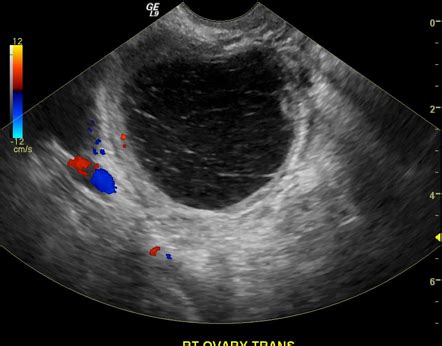

Chisturile ovariene sunt formațiuni apărute pe suprafața unuia sau ambelor ovare. Ele au aspect de săculeți, umpluți cu lichid. Chisturile apar din cauza că pe perioada ovulației, ovulul nu s-a desprins pentru a fi fecundat. Termenul de chist ovarian este unul general. Și asta pentru că din ovar poate să apară orice tip de tumoră, care, atenție: nu înseamnă neapărat cancer! Cu o ecografie transvaginală, se va pune un diagnostic clar despre tipul sau mărimea chistului.

Chisturile ovariene sunt structuri care conțin lichid, ce apar la nivel ovarian. Unele chisturi pot conține și țesut în interior. Chisturile ovariene sunt foarte frecvente și de obicei nu provoacă niciun simptom. Ovarele sunt două organe de mici dimensiuni, care fac parte din sistemul reproducător feminin. Ovarele eliberează un ovul la aproximativ 28 de zile ca parte a ciclului menstrual și secretă hormonii sexuali feminini (estrogen și progesteron), care joacă un rol important în procesul de reproducere. Chisturile ovariene pot afecta ambele ovare în același timp sau pot afecta doar un singur ovar.

- Ecografia pelvină: Ecografia este folosită pentru a confirma prezența unui chist ovarian, pentru a identifica localizarea acestuia și pentru a determina dacă este solid sau dacă este lichid.

Există mai multe opțiuni de tratament, dar abordarea medicală depinde de vârsta pacientei, starea de menopauză, dimensiunea chistului și dacă chistul are caracteristici suspecte de malignitate. Chisturile uniloculare mai mici de 10 cm sunt de obicei benigne, indiferent de vârsta pacientei. Dacă pacienta este asimptomatică, ea poate fi monitorizată prin ecografii transvaginale periodice, deoarece majoritatea chisturilor se rezolvă spontan, fără intervenție.